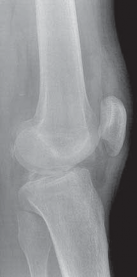

8. Radiographs of the knee should be performed following an acute injury to assess for a fracture. An avulsion of the tibial insertion of the PCL may be identified on a lateral radiograph (

FIG 1A

).

FIG 1 • A. Avulsion fracture of the tibial insertion of the posterior cruciate ligament (PCL). B. Posterior subluxation of the

tibia in a case of chonic PCL deficiency.

1. In the chronic setting, radiographs may identify posterior tibial subluxation (

FIG 1B

) or medial and patellofemoral compartmental arthrosis.